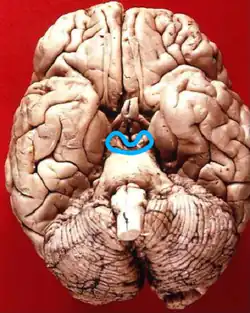

![]() Inferior view in which the midbrain is encircled blue. | |